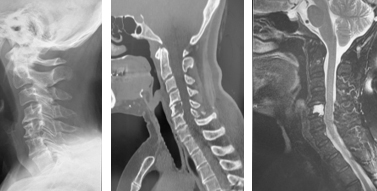

後縦靱帯骨化症、黄色靱帯骨化症

せぼね(脊椎)は7個の頚椎、12個の胸椎、5個の腰椎と仙椎から構成されます。腰椎は主に5つの骨と、間にあるクッションのような椎間板、また神経組織が通っている脊柱管から成り立っています。後縦靱帯骨化症は椎体の後面で脊髄の前にある後縦靱帯が骨化する病気で、黄色靭帯骨化症は脊髄の後ろにある黄色靭帯が骨化する病気で、頚椎が最も発症頻度が高いですが、胸椎や腰椎にも起こり得ます。いずれも根本的な治療法がないことから、厚生労働省難治性疾患克服研究事業の対象疾患に指定されています。白人に比べて東アジアや日本人に多く、頚椎後縦靱帯骨化症は本邦で約3%、男女比はおおよそ2:1ですが、全身性の骨化では女性に多いことが知られています。家族内発症もあることから遺伝的関与の可能性、そのほか肥満や糖尿病との関連も指摘されています。

後縦靱帯の骨化や黄色靭帯の骨化があるからといって、必ずしも神経障害が出るわけではありません。但し、骨化のタイプや大きさによっては、発症や進行をしやすいことがあり、特に転倒による急激な悪化には注意が必要です。局所の症状として、頚部や背部の痛み、また肩こりなどの症状が生じます。脊髄が障害されると、手指の巧緻運動障害(箸が持ちづらい、字が書きづらい、ボタンが上手くはめられない)、痙性歩行(ふらつき・つまずきやすい・歩行がぎこちない)、膀胱直腸障害(頻尿・残尿感)などの症状が生じます。

骨化のタイプや大きさ、不安定性の有無、脊髄の圧迫具合、またせぼね全体のバランスなどを見るためにX線検査やCT検査、MRI検査などを行います。進行例では脊柱管の狭さをより詳しく評価するために入院して脊髄造影検査を行う場合があります。成人期では血管性のしびれがないか評価するために両手足の血圧を測ったり、骨粗鬆症の有無を評価するために骨密度検査を行うこともあります。

肥満や糖尿病がある方は、減量や糖尿病のコントロールをお勧めします。頚部痛などの局所症状に対しては、鎮痛薬やビタミン製剤などの内服、カラー、リハビリテーションなどの保存治療で経過をみます。保存治療で十分な効果が得られない場合、あるいは手足の力が入りづらい(麻痺)、歩行が不安定、また排尿や排便に障害(膀胱直腸障害)がある場合などには手術治療を考慮します。重度の脊髄障害は、不可逆的になり回復が困難となることがあるため、早急な外科的治療を要することがあります。